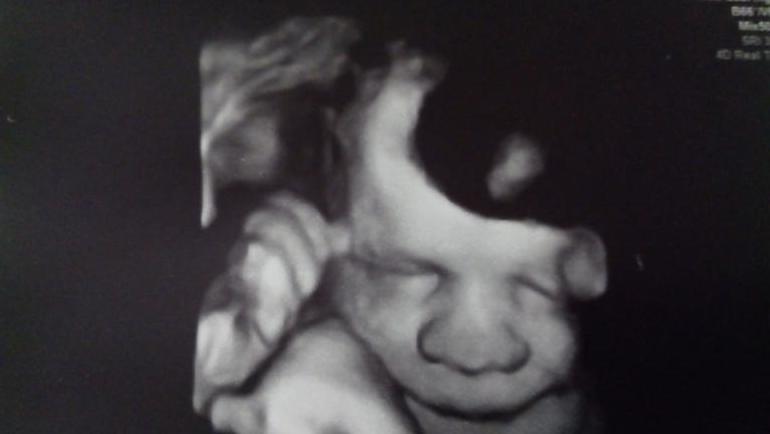

На прошлой недели ходили на УЗИ, все у нас хорошо, идём точно в срок, весит малышка 2180. Узист успокаивала, что вряд ли будет 4000 или 4350, как младшие пацаны, да и плацента уже 2 й степени зрелости, должна быть девчуля до 4 кг. Ну и фото сладули, правда носик расплющен, потому как принималась в сторону датчика

да и вообще словить было тяжело- крутилась, гримасничала)))